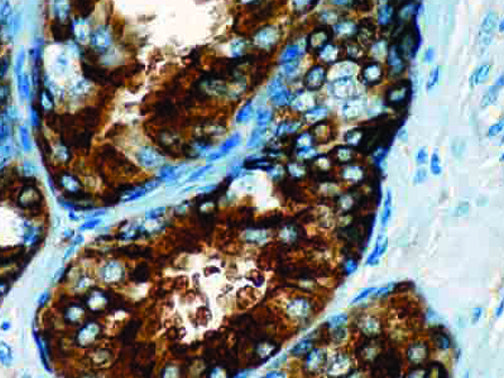

The first cytokines released are interleukin 1β (IL-1β) and tumor necrosis factor-α (TNF-α), which attract a variety of circulating white blood cells (WBCs) to the infection site, including neutrophils, monocytes, macrophages, and natural killer (NK) cells. This response, along with the antipathogenic chemicals released by these cells (i.e., complement), comprise the innate immune response. These cells directly attack the invading pathogen and also release additional cytokines, chief among them interleukin-1 and 6 (IL-6). IL-6 is essential for invoking the adaptive immune response, which calls T-cells, B-cells, and T helper (Th) cells to the infection site. IL-6 also stimulates further recruitment, proliferation and activation of macrophages.

It is the ICU physician who is most likely to witness one of the deadliest manifestations of the abnormal immunological response, the cytokine storm syndrome (CSS). This response is also referred to by some as the cytokine release syndrome (CRS). CSS is characterized by continuous activation and expansion of macrophage and lymphocyte populations, which secrete large amounts of cytokines, causing the cytokine storm. This massive cytokine release is akin to hemophagocytic lymphohistiocytosis (HLH) disease, a syndrome characterized by initial unchecked and persistent activation of cytotoxic T lymphocytes and NK cells.

This activation induces inflammatory monocytes to highly express IL-6, starting a localized and then systemic cascade effect that results in hyperproduction of IL-6, which accelerates the inflammatory process. Because IL-6 also increases vascular permeability, excessive levels cause blood vessels to become very leaky. This, along with clotting factors released from vascular endothelial cells, stimulates the coagulation cascade, resulting in microthrombosis (tiny clots), which leads to ischemia and tissue death of the kidney, intestines, heart, liver, brain and extremities.